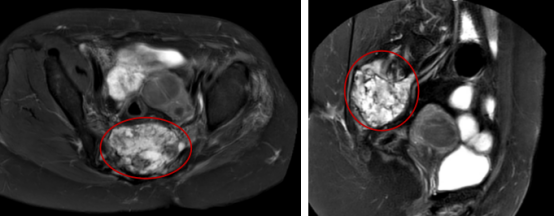

患者王**,女性,52岁,黎族,诊断:骶尾部脊索瘤。治疗前评估:MR-骶2-4椎体部分骨质破坏,相应平面见大小约8.8x7.1cm(S6,I57)混杂T1、混杂长T2肿块影,向盆腔内生长,局部侵及骶管,边界尚清;病灶约270度的范围内紧临结直肠。

2023年3月(碳)离子治疗前核磁检查,红圈内为肿瘤

2023年3月(碳)离子治疗前核磁检查,红圈内为肿瘤

治疗前肿瘤8.8×7.1cm,左图为MRI的T1轴位,中图为T2轴位,右图为T1矢状位